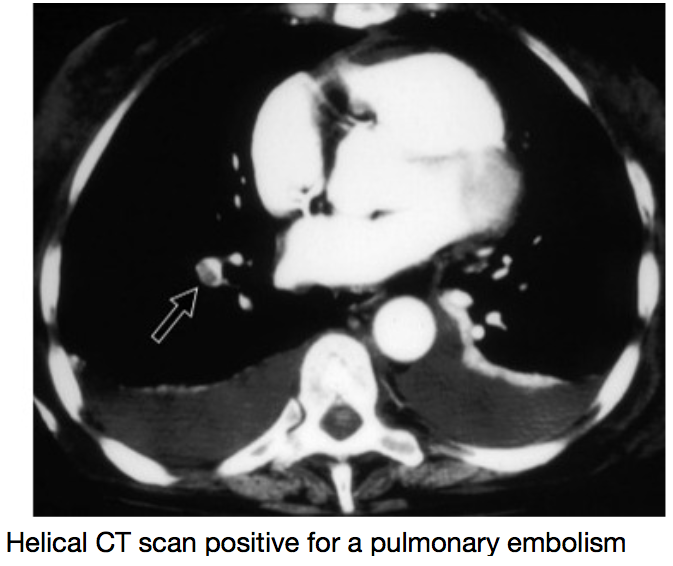

Describe the Approach to a PE pt

Most common sx of Pulmonary Embolism-5

Physical Exam: Rales, low Fever, Hemoptysis